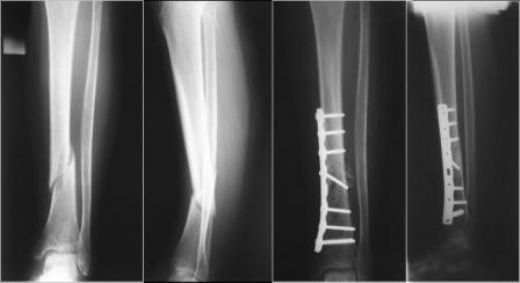

• Çene Kemiği Kırıkları: Travmalar sonucu oluşan kırıklar, çene fonksiyonlarını ciddi şekilde etkileyebilir.